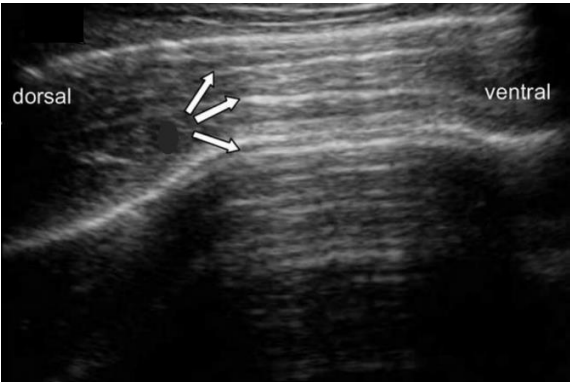

Analise a imagem a seguir.

Nessa imagem de um exame ultrassonográfico, qual é o artefato de imagem indicado pelas setas?